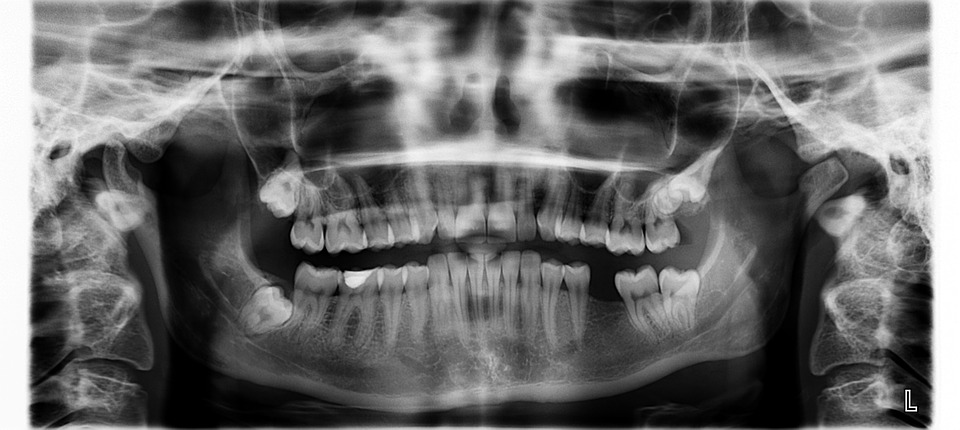

Traditionally, dentists assess the condition of their patients' gums using an instrument called periodontal probe, which is a thin, hook-like metal tool that has labels like a measuring stick and is placed in between the teeth and gums to see how much the gums have shrunk back from the teeth, causing the formation of pockets.

A pocket depth that measures one to two millimeters shows healthy gums while a pocket depth of three mm is indicative of gum disease. The deeper the pockets, the worse the gum disease. (Related: Contrary to what your dentist may tell you, you CAN reverse tooth decay, new research finds.)

However, the researchers mentioned that dentists often measure pockets differently, and that the probhe can only measure the pocket depth of one spot at a time.

This technique makes it possible for dentists to visualize a full map of the pocket depth around each tooth – a remarkable improvement over the traditional method.

Researchers said the results of the photoacoustic imaging method were consistent across multiple tests, unlike when the assessment was done with the periodontal probe, wherein results varied from one test to another.